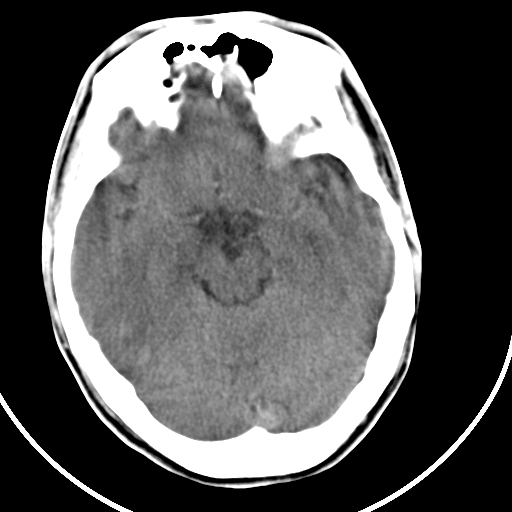

标题: CT21939:男20岁,外伤一年后,现头疼. [打印本页]

标题: CT21939:男20岁,外伤一年后,现头疼.

颅骨凹陷性骨折并压迫脑组织致大脑镰下疝!

硬膜外血肿机化

硬膜外血肿伴包膜钙化

左侧额部硬膜外血肿机化、骨化。

左侧额部硬膜外血肿机化、骨化